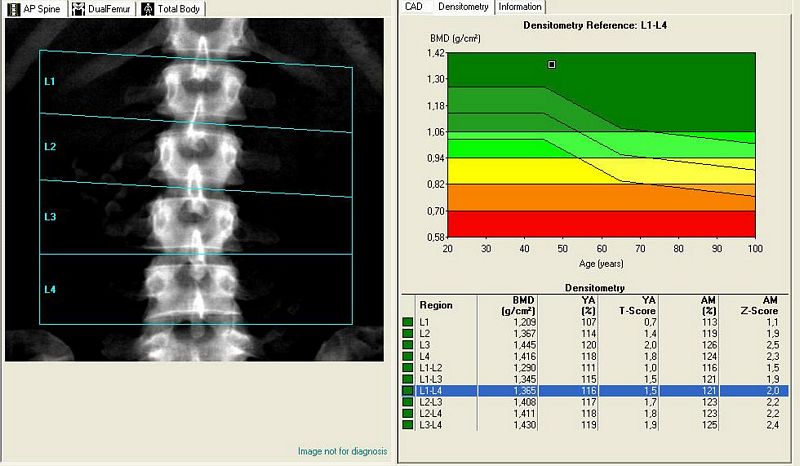

• Δωρεάν μέτρηση οστικής πυκνότητας σε άνδρες και γυναίκες όλων των ηλικιών, κατόπιν ραντεβού. Οι μετρήσεις θα γίνουν στην Αίθουσα Πολλαπλών Χρήσεων του Γυμνασίου - Λυκείου Δομοκού την Παρασκευή 15/04/2016, ώρες 16:00 έως 20:00 και το Σάββατο 16/04/2016, ώρες 12:00 έως 17:00. Επίσης στο Διοικητήριο Θεσσαλιώτιδος (πρώην Δημαρχείο) την Κυριακή 17/04/2016, ώρες 11:00 - 16:00